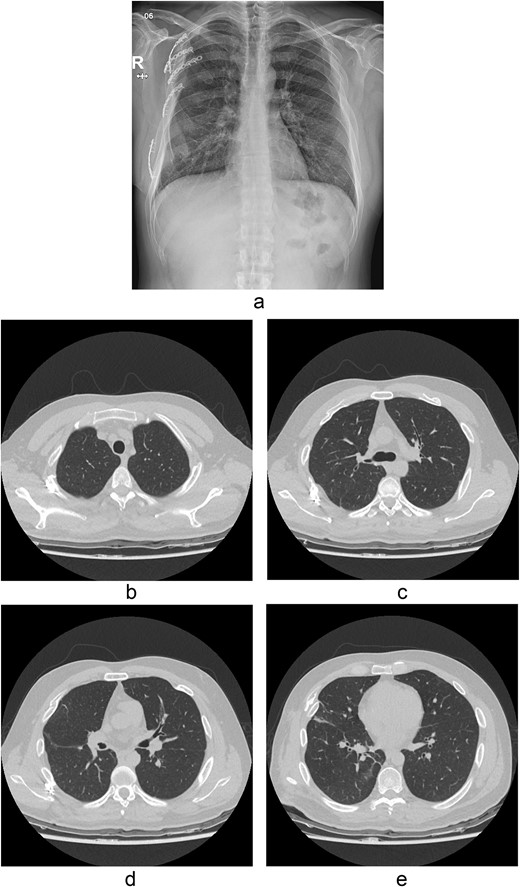

A contrast-enhanced chest CT scan after blunt chest trauma. Chest radiograph showed right hemopneumothorax and left hydropneumothorax. Multifocal extensive hemorrhage/pneumatocele formation was visible on the right side along with combined active bleeding (arrows) in the right lung.

The thoracotomy incision was relatively small, ~8 cm in size, and the intercostal space was not spread to prevent further intraoperative chest wall damage. There were multiple lung lacerations in the upper, middle, and lower lobes with active bleeding. Bloody leakage continued through the avulsed parietal pleura and mediastinum. Hemostasis was achieved by suturing the deeply lacerated lung and packing with gauze (Combat Gauze ™ [Z-Medica QuikClot]) at the chest wall and mediastinum. The operation took 130 minutes. The transfusion of plasma, platelets, and red blood cells was balanced according to the following quantities: 10, 10, and 14 U, respectively. After surgery, the patient was transferred to the intensive care unit (ICU). The PaO2/FiO2 ratio was 52 mmHg with a Positive end expiratory pressure of 15 cm H2O, at a peak inspiration pressure of 30 cmH2O. ABGA showed pH 7.23, pCO2 42, and pO2 47. Veno-venous ECMO based on bilateral femoral vein cannulation was performed (Fig. 3a). Considering the patient’s hemorrhagic predisposition, heparin was not used. Disseminated intravascular coagulation (DIC) occurred along with acute renal failure. Antithrombin III infusion and continuous renal replacement therapy (CRRT) were initiated on the second hospital day. By the 5th day, oxygenation was achieved without ECMO support, followed by decannulation. On the 6th day, the second operation was performed in about 35 minutes. The gauze was removed, and no active bleeding or oozing was seen (Fig. 3b). The third operation, performed on the 13th day, was an open reduction of right ribs 3–7 for correction of flail chest and took 75 minutes (Fig. 3c). After open reduction, the flail chest improved, but the patient was not able to be weaned off the ventilator. Pneumonia and bacteremia developed. A tracheostomy was performed on the 15th day. CRRT was switched to hemodialysis, which was stopped on Day 28. The patient was discharged on the 47th day without tracheostomy. Ten months postoperatively, pulmonary function testing revealed forced expiratory volume in one second and diffusion capacity of carbon monoxide of 77% and 67% of predicted values, respectively. The chest CT and radiographs showed that the lungs had healed well, and there was no displacement of the ribs (Fig. 4). The patient recovered and returned to work.

Chest radiograph and CT scan 10 months after the accident. (a) Chest radiograph showed well-healed fractured ribs and expanded lungs without active lesions. (b)–(e) Non-enhanced axial chest CT images showed recovery from injury.